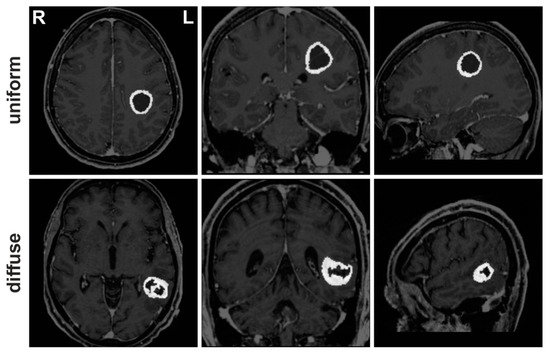

| Total | Uniform Tumor Growth Pattern | Diffuse Tumor Growth Pattern | Sig. | ||

|---|---|---|---|---|---|

| Verb generation | n | 64 | 23 | 41 | |

| Age | 59.84 | 62.87 | 58.15 | 0.114 | |

| Sex (m/f) | 37/27 | 13/10 | 24/17 | ||

| Tumor location (frontal/parietal/temporal) | 5/4/14 | 13/9/19 | |||

| Tumor size in mm3 | 22,707.65 | 35,876.75 | 0.031 * | ||

| Edema size in mm3 | 52,534.35 | 56,229.12 | 0.707 | ||

| Antonym generation | n | 47 | 16 | 31 | |

| Age | 59.66 | 62.31 | 58.29 | 0.274 | |

| Sex (m/f) | 26/21 | 9/7 | 17/14 | ||

| Tumor location (frontal/parietal/temporal) | 2/4/10 | 9/8/14 | |||

| Tumor size in mm3 | 24,437.44 | 36,302.55 | 0.098 | ||

| Edema size in mm3 | 58,471.71 | 57,401.19 | 0.926 | ||

| Syntax generation | n | 57 | 22 | 35 | |

| Age | 59.86 | 63.90 | 57.83 | 0.095 | |

| Sex (m/f) | 33/24 | 13/9 | 20/15 | ||

| Tumor location (frontal/parietal/temporal) | 5/4/13 | 8/9/18 | |||

| Tumor size in mm3 | 22,536.14 | 34,112.34 | 0.076 | ||

| Edema size in mm3 | 52,936.82 | 54,296.62 | 0.894 |